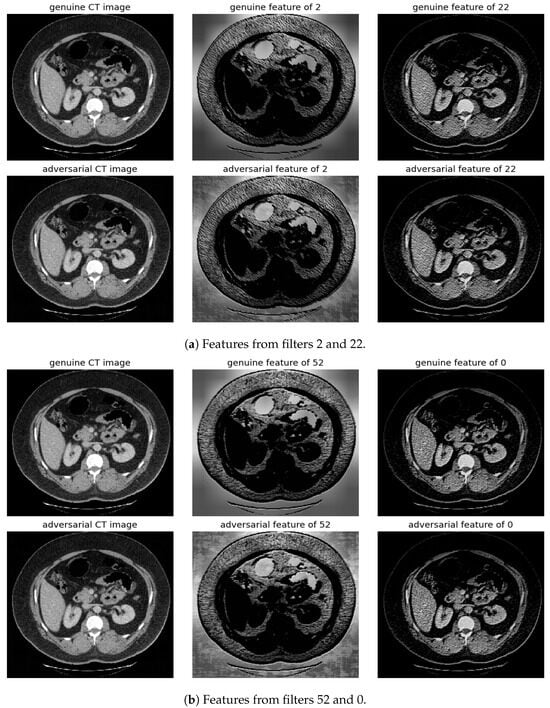

Randomly selected genuine CT samples, alongside their adversarial versions, are displayed in Figure 9, Figure 10 and Figure 11. The adversarial samples were generated using FGSM, BIM, and SMIA attack methods, each with an epsilon of 0.01. While BIM and SMIA used 5 iterations, FGSM did not. These samples represent the most challenging scenarios for human visual detection. Despite the modest epsilon value, as indicated in Table 3, the adversarial attacks have a subtle but pronounced effect. Such slight modifications can lead to major diagnostic inaccuracies potentially impacting patient care.

Figure 11.

Visualization under SMIA Attack: Comparison of features from the first layer between genuine and adversarial samples for the most sensitive (filters 2 and 52) and least sensitive (filter 22 and 0) filters.

To address this, histogram equalization as feature post-processing is applied. The visual representations underscore that while genuine and adversarial samples might appear similar to the naked eye, post-processing brings forth distinct feature differences when employing the most sensitive filters from 2 and 52. Perturbations, especially noticeable in the background of the adversarial samples, are frequently highlighted by these filters. Conversely, features processed with filters from 22 and 0, deemed less sensitive in prior analyses, fail to offer a stark visual contrast.